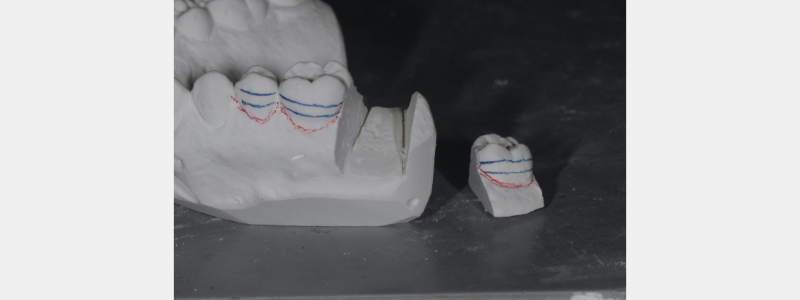

Separate the distal tooth from the stone model using a plaster saw or a rotary disc. Separate the tooth directly at the stone model’s mesial and distal contact points (Fig. 3). Once the vertical cuts are complete, detach the tooth by making a horizontal cut approximately 2-3 mm gingival to the facial/buccal gingival margin. I utilize a plaster saw for the vertical cuts, followed by a lab engine and a #557 straight shank cutting tool for the horizontal sectioning.

The separated tooth is then reset in the stone cast with wax (Fig. 4). If needed, the proximal contact of the freed tooth is contoured to allow for increased tightness and sufficient contact closure. This tooth is secured with pink baseplate wax. The scribed lines allow for proper positioning in a vertical dimension.